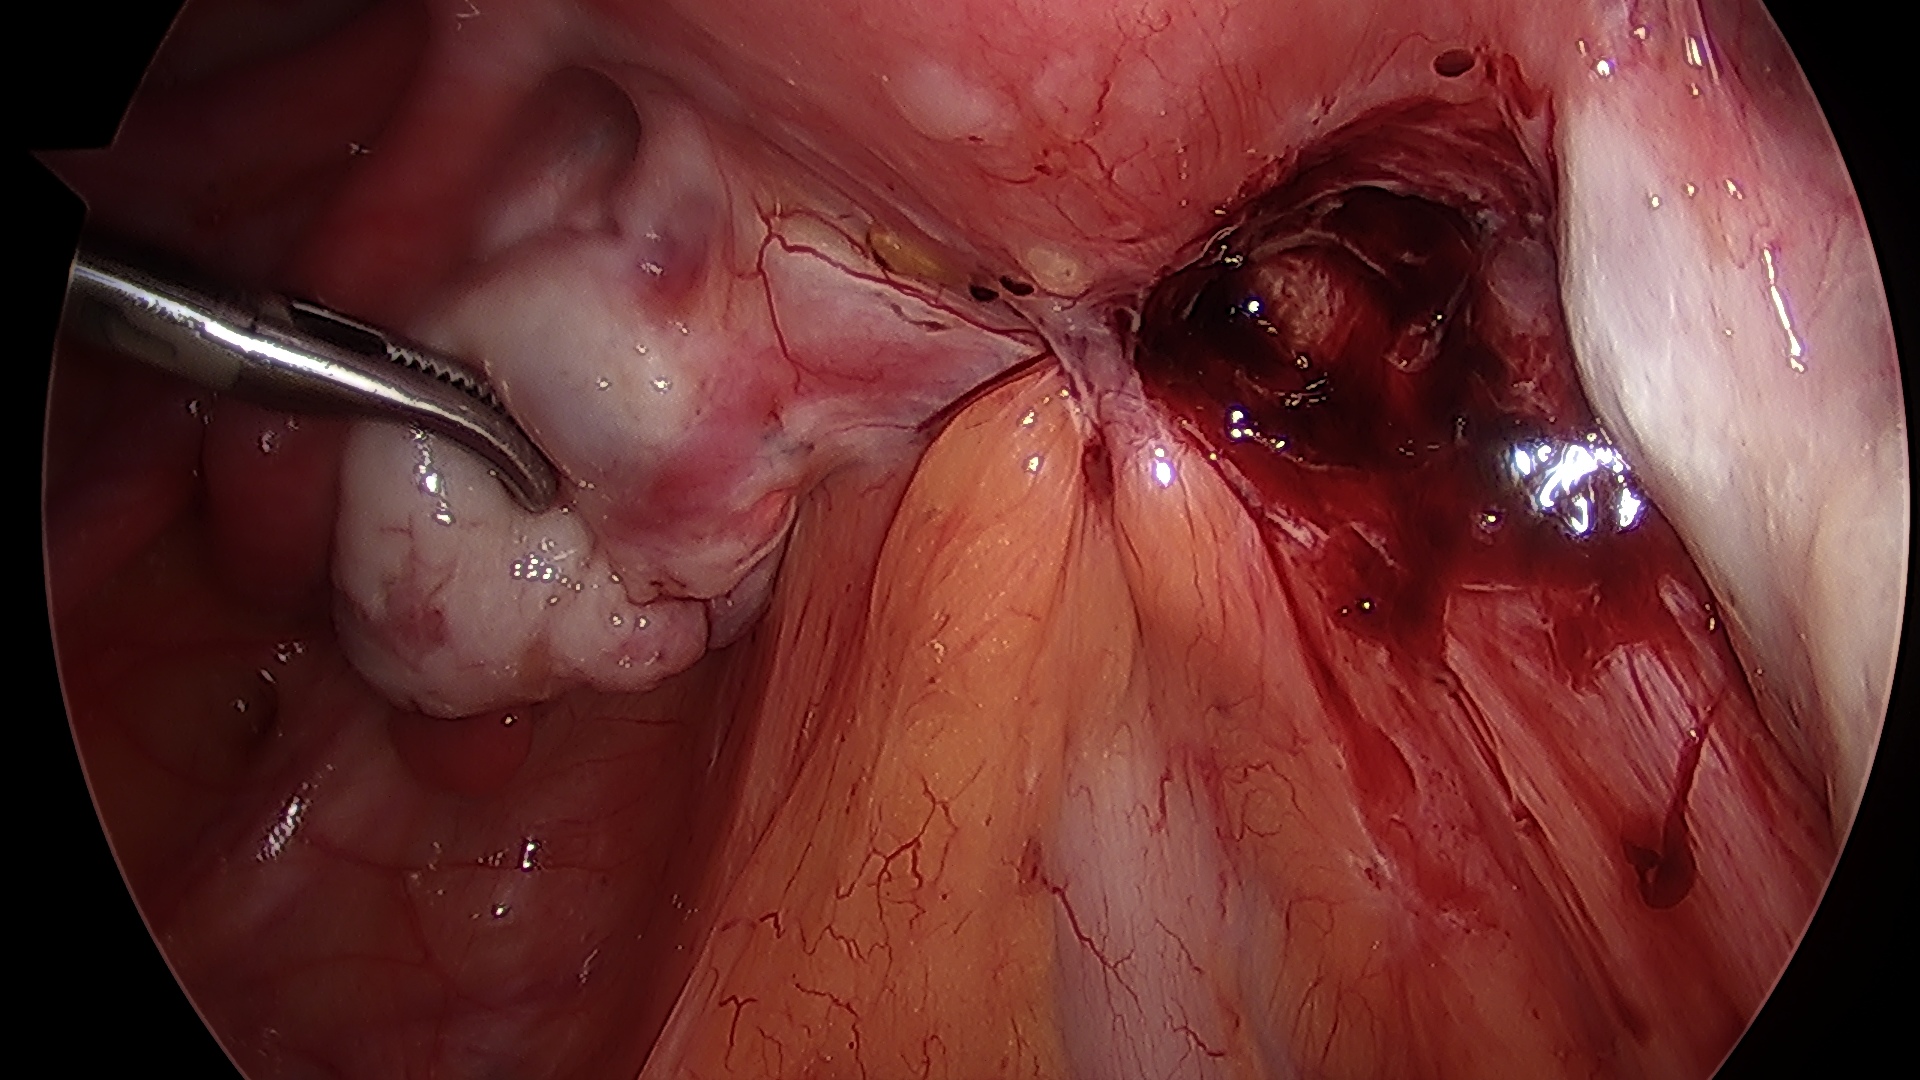

A fecundação do óvulo ocorre na trompa e a partir de então, com os movimentos peristálticos, esse óvulo fecundado é direcionado para o útero, Na gravidez tubária, notamos uma falha nesses movimentos, fazendo com que a gestação se desenvolva no interior da trompa. Com o avançar da gravidez, ocorre a dilatação da trompa, acompanhada de dor importante na parte baixa do abdômen. Eventualmente, essa dilatação ocorre de tal forma que a tuba uterina acaba rompendo (rota) e provocando hemorragia abdominal, exigindo intervenção cirúrgica rápida. A laparoscopia é excelente via de acesso para o tratamento da gravidez tubária.